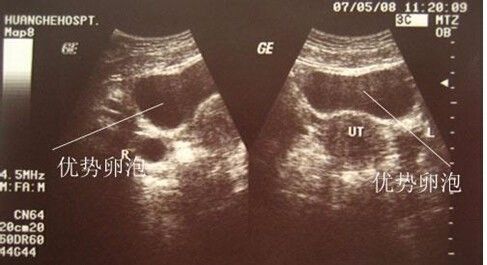

很多备孕女性去医院B超监测排卵,医生建议其在卵泡长到1.8~2.5毫米的时候同房,但连续几个月都是这样也没怀上。后来才知道卵泡没有正常继续发育,或者是卵泡发育成熟但也无法排出,导致不能顺利怀孕。卵泡发育情况,是很多备孕女性十分关注的问题。若卵泡发育不良、无法排出就会影响备孕的进程和结果。可以说,卵泡发育问题很重要。那么,有哪些因素会影响卵泡发育呢?

2、卵泡小:卵泡发育不成熟,直径常常小于18毫米。

4、卵泡不破裂:卵泡发育成熟,但是不破裂,无法排卵。